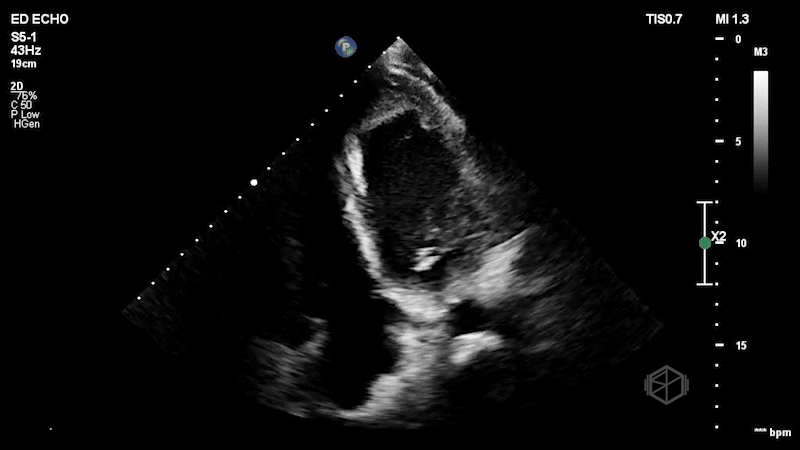

Contrast echo showing apical LV thrombus.